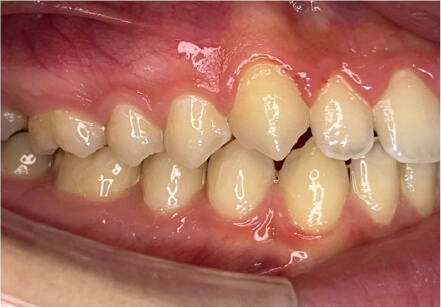

叢生の症例

41歳

/

女性

相談内容

横から見た時のガタガタが気になる

カウンセリング・診断結果

インビザライン、正中は上11に合わせていく、抜歯・拡大装置・IPR・アタッチメントOK

治療内容・方法

アライナー矯正

術後の経過・現在の様子

クリアライナー使用

治療のリスク

痛み・歯根吸収・歯肉退縮・虫歯・後戻り

費用・治療期間

880,000円、7ヶ月

トレーニングなど